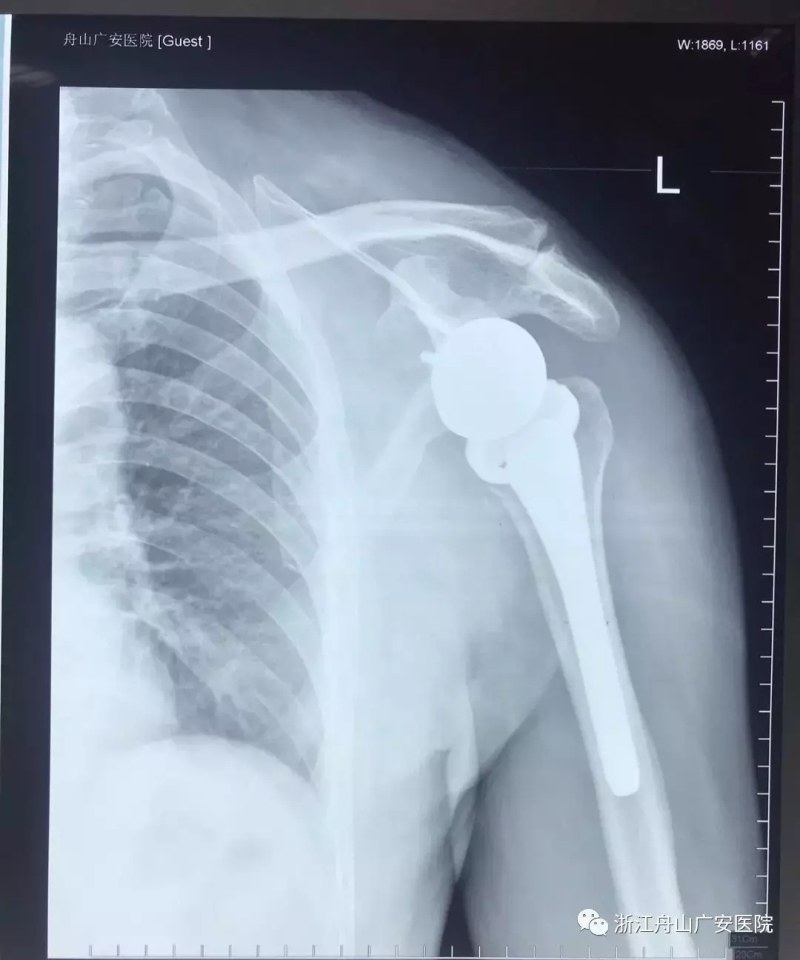

經(jīng)過(guò)術(shù)前精心的手術(shù)準(zhǔn)備,羅軍主任帶領(lǐng)手術(shù)專家團(tuán)隊(duì)為張大伯做了反式人工肩關(guān)節(jié)置換術(shù)。手術(shù)過(guò)程十分順利,僅用時(shí)一個(gè)半小時(shí),且手術(shù)刀口很小,約10cm,術(shù)后恢復(fù)快,第二天查房時(shí)候張大伯便能佩戴特制的肩肘墊起床活動(dòng),術(shù)前肩關(guān)節(jié)劇痛也大大緩解減輕,術(shù)后兩周患者功能恢復(fù)良好。

反式肩關(guān)節(jié)置換術(shù)后照片